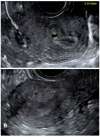

Endometriosis has a prevalence of 10% worldwide in premenopausal women. Probably, endometriosis begins early in the life of young girls, and it is commonly diagnosed later in life. The prevalence of deep infiltrating endometriosis (DIE) in adolescence is currently unknown due to diagnostic limits and underestimation of clinical symptoms. Dysmenorrhea is a common symptom in adolescents affected by DIE, often accompanied by dyspareunia and chronic acyclic pelvic pain. Ultrasonography-either performed transabdominal, transvaginal or transrectal-should be considered the first-line imaging technique despite the potential for missed diagnosis due to early-stage disease. Magnetic resonance imaging should be preferred in the case of virgo patients or when ultrasonographic exam is not accepted. Diagnostic laparoscopy is deemed acceptable in the case of suspected DIE not responding to conventional hormonal therapy. An early medical and/or surgical treatment may reduce disease progression with an immediate improvement in quality of life and fertility, but at the same time, painful symptoms may persist or even recur due to the surgery itself. The aim of this narrative review is to report the prevalence of DIE in adolescents, describe the pathogenetic theories and discuss the management in adolescent women, including the challenging road to diagnosis and the treatment alternatives.